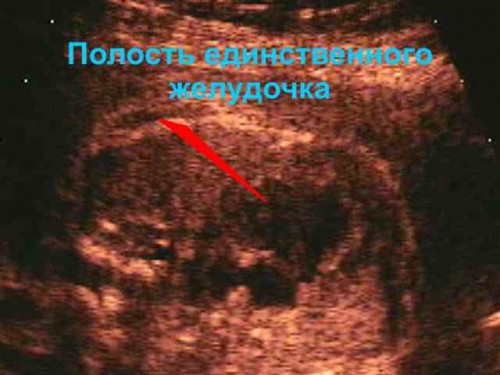

Идейным вдохновителем и организатором коллегиального общения специалистов УЗД всех родильных домов и женских консультаций является Сергей Серман, один из самых опытных акушеров-гинекологов города Магнитогорска. Главной темой обсуждения на этот раз стала диагностика редкого случая патологии сердца плода. Сергей Николаевич подробно рассказал коллегам, как выявил редчайший порок развития – «единственный желудочек сердца».

«В МОПД из района приехала женщина на второй скрининг по беременности. Я диагностировал у плода отсутствие одного из желудочков сердца. Вместо четырех камер в сердце было всего три. Это очень редкий порок развития, который в настоящее время не поддается хирургическому лечению. Пациентка была направлена в Челябинский областной перинатальный центр для прерывания беременности».

Согласно общемировой статистике, около 60 % всех пороков внутриутробного развития плода приходится именно на проблемы с сердцем. Диагностировать их очень сложно. Многолетний опыт и «зоркий глаз» профессионала, а также ювелирная тонкость в использовании технических достижений в диагностике и лечении пациентов позволили Сергею Серману увидеть не только отсутствие одной из четырех камер сердца. Весной этого года Сергей Николаевич впервые в истории магнитогорской медицины диагностировал брюшную беременность у пациентки, которая впервые обратилась к гинекологам на сроке 32 недели. В результате оперативного родоразрешения в Челябинске появился на свет здоровый ребенок. Это был 19-й случай рождения ребенка после брюшной беременности в мировой медицинской практике.